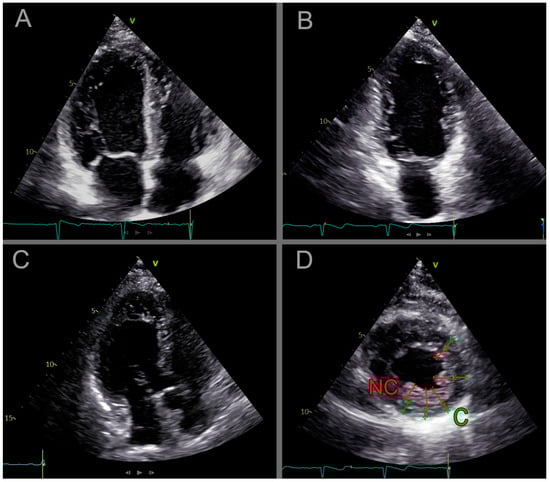

2.2.3. Cardiac Ultrasound